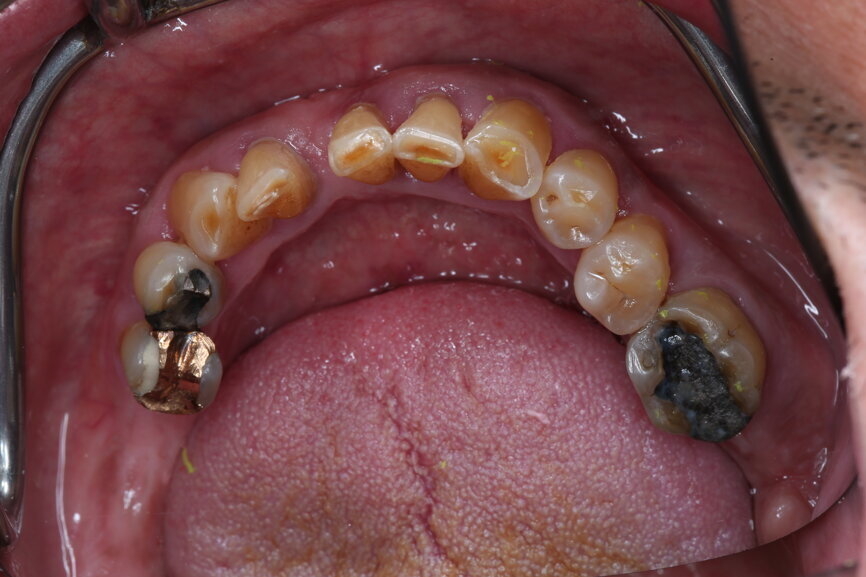

A 51-year-old male patient who was a smoker (< 10 cigarettes per day) and in good general health presented to the clinic with missing molars in the second and fourth quadrants, Grade III mobility of teeth #24 and 17, decayed roots and gingival inflammation, and without abscess or sinusitis of tooth #16. The anterior zone showed  different extents of recession, bone resorption and deep periodontal pockets around teeth #12 and 22, which led to the patient complaining about an aesthetically unsatisfying restoration (Figs. 1 & 2).

Initial situation